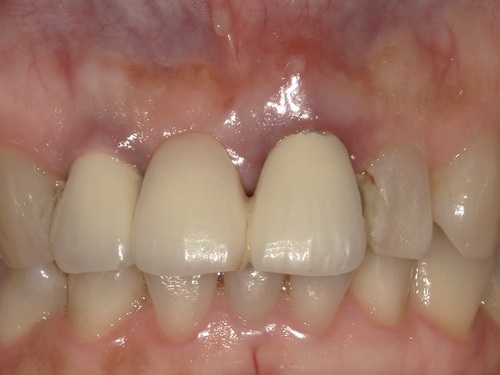

こちらが初診時のレントゲンとお口の写真になります。

右上の1番目の歯がすでになく、右上の2番目と左上の1番目の歯でブリッジが入っている状態です。ブリッジは、他の歯の色に比べ、白く不自然な色となっています。さらに、左上1番目の歯茎が腫れてしまっているのが良くわかります。

適合・色合い・噛み合わせに問題がないことを確認し、歯科用セメントでしっかりとセットしました。術前と比較して色も自然でとても美しい仕上がりかと思います。

初診時にはインプラント治療にするかブリッジ治療にするか大変悩まれておりましたが、綺麗なブリッジが入って、患者様は今回の治療に大変満足されております。また保険外治療で高額な治療とはなりましたが、とても綺麗な歯が入ったと『ジルコニアセラミックにして良かった』とおっしゃられておりました。